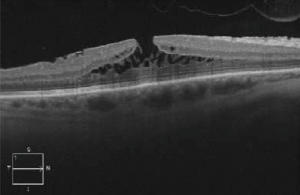

OCT imaging showing the partial loss of inner foveal tissue is diagnostic. Fundus autofluorescence can also show hyperautofluorescence due to a window defect in the macular area from the loss of foveal tissue.

OCT diagnostic criteria for LMH have undergone multiple changes over time. The most widely used 2006 criteria adopted by the International Vitreomacular Traction Study Group included:

- An irregular foveal contour;

- A break in the inner fovea;

- Dehiscence of the inner foveal retina from the outer retina;

- The absence of a full-thickness foveal defect with intact foveal photoreceptors[15][16].

Govetto et al. subsequently divided LMH into “tractional” and “degenerative” categories with a minimum of 3/5 diagnostic criteria for each type (see table)[4]. If it fails to correspond to either category, the lesion is classified as “mixed”.

The newest consensus made by Hubschmann et al. distinguishes LMH presenting with tractional, contractile ERM by identifying them as ERM foveoschisis (ERMF)[16]. LMH presenting with degenerative configuration are simply referred to as LMH.

| OCT imaging |

OCT is the gold standard for diagnosing and managing LMH with findings as described above. Fundus autofluorescence can also be performed which shows hyperautofluorescence through loss of foveal tissue leading to a window defect.